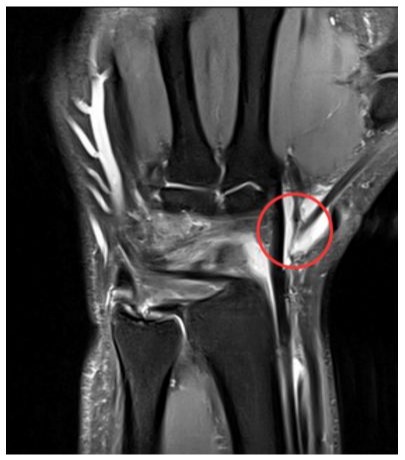

A 36-year-old male patient visited our clinic, complaining of right wrist pain. He was an office worker and had no medical history on his right wrist. He rode his bicycle and bumped into a car which was parked in a street one day before the visit. The handle of the bicycle hit his palm quite hard making his wrist hyperextended. Physical examination revealed moderate tenderness and swelling on the dorsal aspect of the wrist. Active motion, especially dorsiflexion was limited due to pain. However, the plain radiographs at initial visit showed no definite fracture at his right wrist but soft tissue swelling of the wrist dorsum (Figure 1). We diagnosed it as a wrist sprain and put a short arm splint on his right wrist. We checked plain radiographs again 2 weeks after the injury. As we confirmed that there was no fracture identified on the plain radiographs, we removed the splint and let him return to his daily activity. However, he visited our clinic 5 weeks after injury, complaining of inability to actively extend his right thumb. Physical examination showed loss of active extension of thumb interphalangeal joint. On MRI, an EPL tendon was ruptured around the Lister’s tubercle (Figure 2), although there was no signal change of distal radius or other carpal bones, suggesting a bone contusion or a microfracture. The distal stump was identified around the 1st carpo-metacarpal joint, and the proximal stump was not definitely delineated. Abundant fluid collection was observed around the ruptured tendon ends (Figure 2).

Figure 2: On MRI (T2 Coronal), an EPL tendon rupture was observed and the distal stump was identified around the 1st carpometacarpal joint (red circle). Fluid collection was observed around the ruptured tendon ends and there was no signal change of distal radius or other carpal bones, suggesting a bone contusion or a micro-fracture.

There are two major mechanisms explaining the pathogenesis of spontaneous rupture of the EPL tendon. One is mechanical theory and the other is vascular theory [1,6]. According to the mechanical theory, the EPL tendon courses over the dorsal cortex around Lister’s tubercle and the rough bony edge at the distal radius fracture abrades the EPL tendon [1,7]. The vascular theory says that the increased pressure within the tendon sheath at Lister’s tubercle causes ischemia and delayed rupture of the EPL tendon [1,6,7]. In our patient, we could not find a definite fracture of distal radius or carpal bones not only on x-ray but also on MRI. MRI showed that EPL tendon rupture around the Lister’s tubercle and abundant fluid collection around the torn tendon ends. Thus, we presumed that significant hematoma caused by a dorsiflexion injury of a wrist led to subsequent pressure increase on the EPL tendon, which resulted in EPL the tendon rupture.